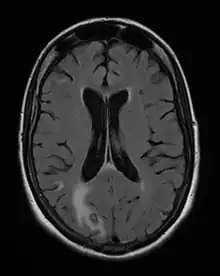

MRI: Cerebral toxoplasmosis with primary involvement in the right occipital lobe (at left and below of the image). 48-year-old woman with AIDS

Diagnosis of toxoplasmosis in humans is made by biological, serological, histological, or molecular methods, or by some combination of the above.[62] Toxoplasmosis can be difficult to distinguish from primary central nervous system lymphoma. It mimics several other infectious diseases so clinical signs are non-specific and are not sufficiently characteristic for a definite diagnosis. As a result, the possibility of an alternative diagnosis is supported by a failed trial of antimicrobial therapy (pyrimethamine, sulfadiazine, and folinic acid (USAN: leucovorin)), i.e., if the drugs produce no effect clinically and no improvement on repeat imaging.